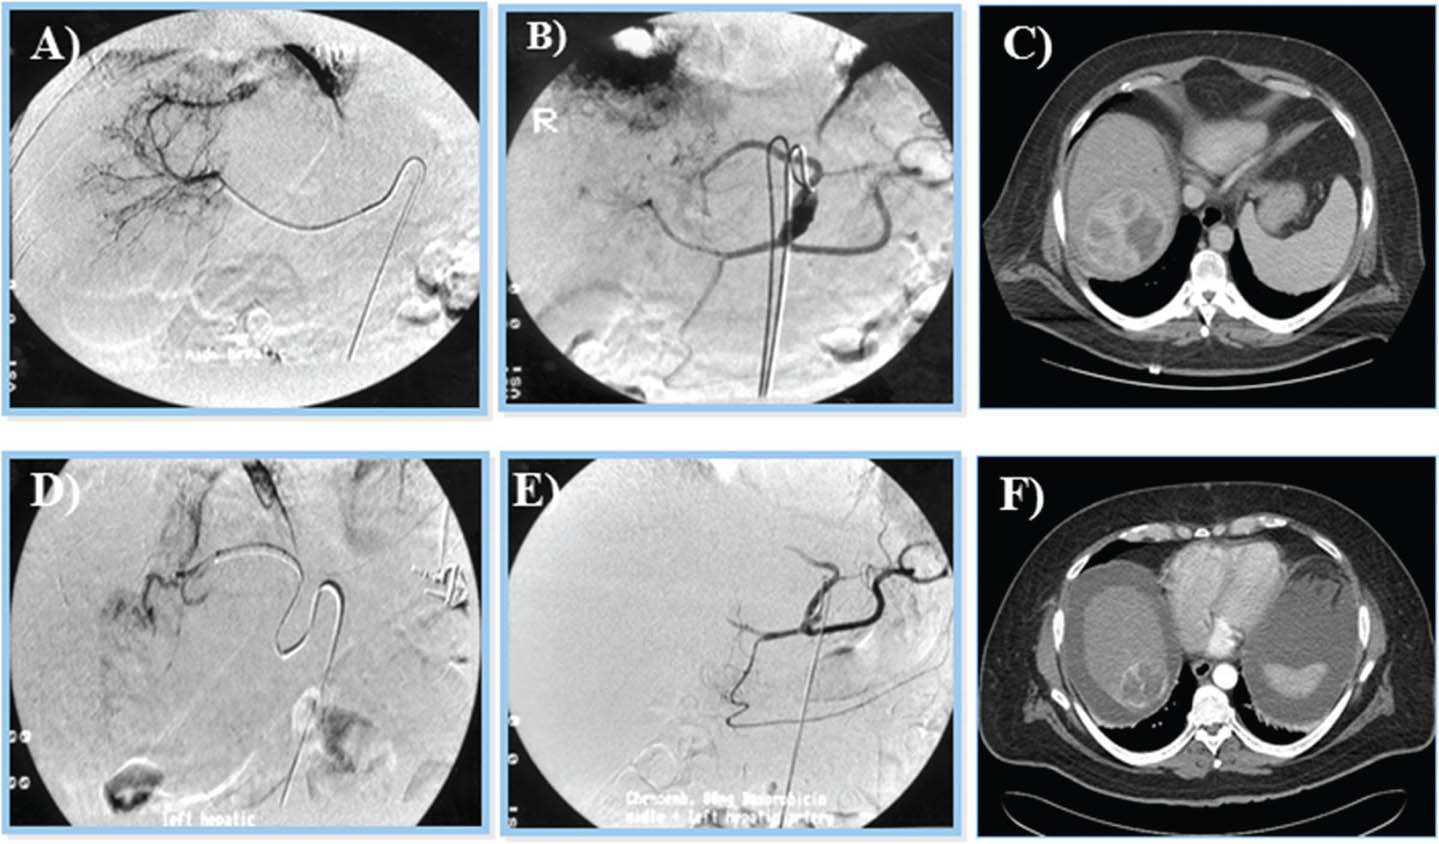

Fig 10

Figure 10. Trans-arterial chemoembolization of the liver for hepatocellular carcinoma. A and B. Selective arterial embolization of the vessels feeding the tumor in the liver. C. Tumor visualized by CT scan. The procedure is performed with or without chemotherapy. D and E. After embolization, angiography showed obliteration of feeding vessels with shrinkage of the tumor. F. Follow up CT scan after embolization. Note an increase in patient’s ascites.